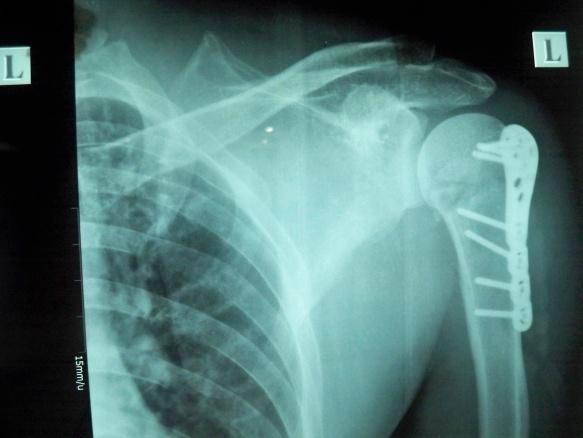

左肱骨外科颈骨折伴左肩关节脱位

患者男,43岁,从约3米高处坠落,左肩关节及上臂肿胀、疼痛活动受限3天入院。

查体:一般状况好,神志清楚,自动**。体温37.1℃,脉搏、呼吸、血压正常。头颅五官胸腹未见异常。脊柱无畸形及压痛。左肩关节明显肿胀,无皮肤裂口,可见大量皮肤瘀斑。左肩关节活动受限。左上肢皮肤浅感觉正常。左手各指感觉正常,左肩处叩击疼。